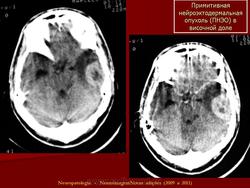

ГМ. Примитивная нейроэктодермальная опухоль (ПНЭО). +

Примитивная нейроэктодермальная опухоль (ПНЭО)